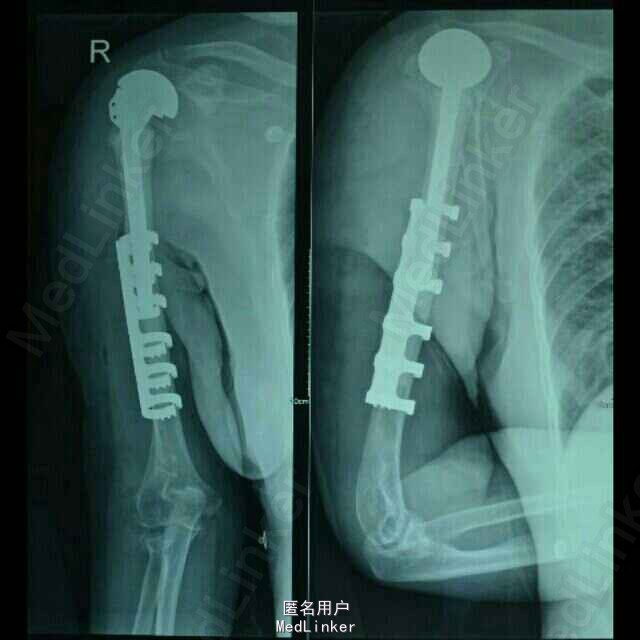

专科检查:右肩关节前内侧见一长约15cm的斜行手术疤痕,愈合良好,局部无红肿及压痛,右侧肩关节未见明显畸形,功能活动尚可,因上臂牵涉性疼痛活动受限,肩部无异常触痛;右上臂肿胀、畸形明显,皮肤张力稍高,局部假关节形成,局部皮肤无破损,未见明显挫伤痕迹,皮温正常,触痛明显,以右肱骨干中段处为甚,可扪及明显的骨摩擦感及异常活动;右肘关节无红肿及压痛,右肘关节伸直活动受限约30度,屈曲活动正常,右前臂活动正常;右上肢纵向叩击痛(++),患肢末梢循环、感觉、活动正常。 DR示:右侧人工肱骨头置换术后伴假体周围骨折,慢支炎肺气肿伴左侧胸腔积液。 颅脑MRI示:两侧基底节区陈旧性腔梗。

诊断:1、右侧人工肱骨头置换术后伴假体周围骨折 2、慢性肺气肿伴左侧胸腔积液 3、双侧脑基底节区陈旧性腔隙性脑梗塞灶 4、血压病(2级 高危层) 5、骨质疏松症(重度) 6、右髋关节置换术后 治疗: 因患者高龄,基础疾病较多,较重,故手术风险大,经呼吸内科,心血管内科及神经内科会诊及治疗处理后,患者内科病情控制稳定,予行手术治疗,术中检查,右肩关节假体无松动,故单纯予行假体周围骨折固定术治疗。

随访:术后1周指导患者功能锻炼,术后1月患肢功能基本恢复正常。讨论:患者系人工肩关节假体周围骨折,骨折远近段髓腔内填充有骨水泥,骨折端髓腔血运中断,故保守治疗效果欠佳,容易发生骨折多次移位,复位及固定困难,容易并发骨折延迟愈合,甚至不愈合,故应考虑积极手术治疗,早其有效固定骨折,并行局部植骨,有利于骨折生长及愈合;同时因患者右肱骨髓腔内骨水泥及金属假体填充,钻孔困难,钢板螺丝钉内固定术难度较大;同时不排除假体松动可能,故根据患者病情及具体情况,拟定手术方案:1、若假体松动,则行关节翻修,予更换加长柄假体,同时骨折部位记忆合金环抱器内固定;2、若术中假体无松动,则直接行“假体周围骨折切开复位记忆合金环抱器内固定术。